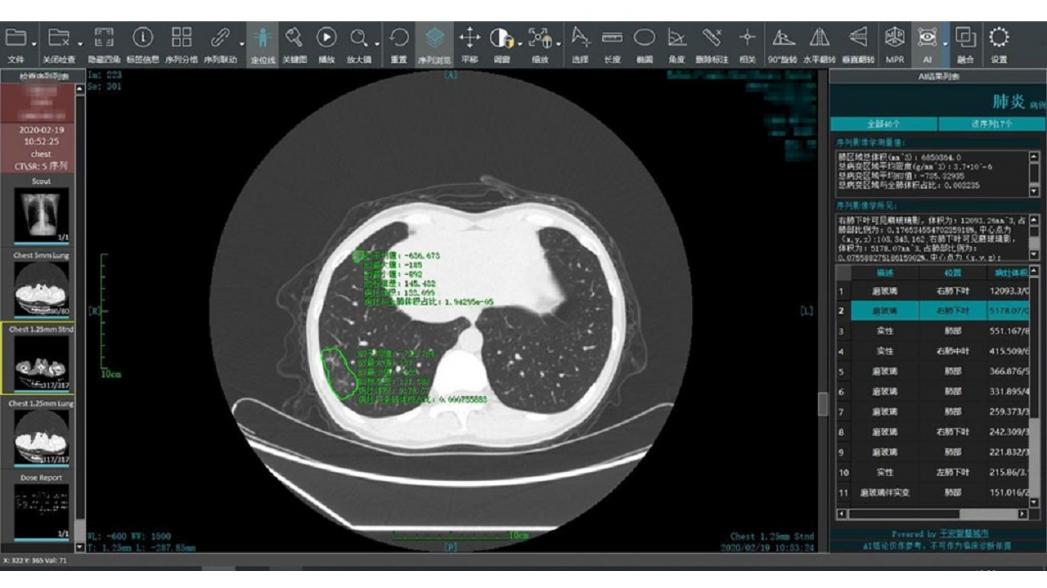

Китайская компания Ping An Insurance запустила в действие систему интеллектуальной обработки КТ-изображений, разработанную компанией Ping An Smart Healthcare для ускорения диагностики и лечения коронавирусной инфекции. Система помогает врачам быстро и эффективно поставить точный диагноз, используя технологию искусственного интеллекта Ping An.

Эта система анализа на основе алгоритма искусственного интеллекта может проводить сравнительный анализ нескольких изображений одного и того же пациента, полученных методом компьютерной томографии грудной клетки, и измерять изменения в легких. Она помогает врачам отслеживать развитие болезни, оценивать лечение и получать прогноз развития болезни для пациентов, т.е. помогает врачам быстро и эффективно диагностировать, сортировать и оценивать перспективы пациентов с COVID-19.

Аналогичная система была совместно разработана Шанхайским клиническим центром общественного здравоохранения и шанхайским стартапом Yitu Healthcare. С помощью этой новой системы на базе искусственного интеллекта можно автоматически определить область поражения и провести количественный анализ за 2-3 секунды.